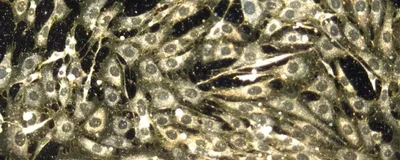

The most recent breakthroughs in getting drugs into the body is using nanoparticles. These materials – which can be made from lipids, proteins, gold or other components – have the advantage of being very small: The diameter of a typical nanoparticle is about 10-thousandths of a millimeter. Their small size allows diseased cells to easily take them up. So when nanoparticles contain drugs, they can act as a drug delivery system.

Despite being so small, nanoparticles can hold a large number of drug molecules, allowing them to deliver a potent cargo of treatment directly into a cell. They can also deliver drugs made of DNA and RNA.5 The most well-known example of this technology is the COVID-19 vaccine, which uses nanoparticles made of modified fat molecules to deliver mRNA that teaches the immune system to protect itself against COVID-19 infection.